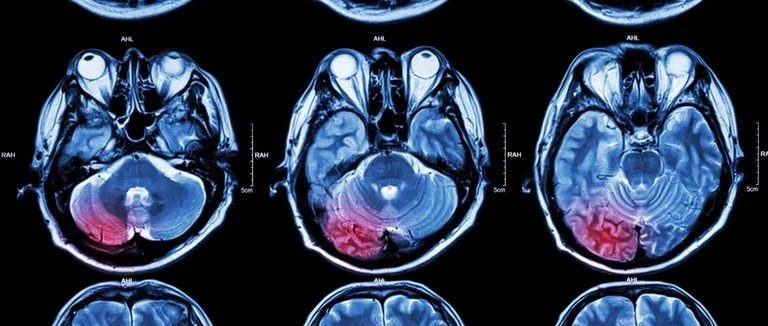

Tumeurs Cérébrales et Système Nerveux Central

L'IRM est très bonne pour trouver les tumeurs du cerveau et du système nerveux. Elle montre bien la taille, la forme et l'emplacement des tumeurs. Cela aide à choisir le bon traitement.

Les tumeurs du cerveau, bonnes ou mauvaises, sont trouvées avec précision par l'IRM. Cette technique est très utile pour les gliomes, les méningiomes et les neurinomes.